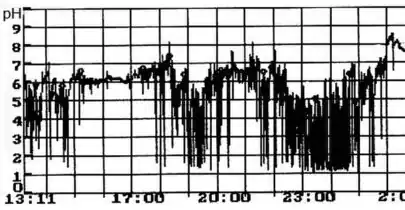

Внутрижелудочная pH-метрия играет важнейшую роль при диагностике и лечении кислотозависимых заболеваний, при исследовании гастроэзофагеальных, дуоденогастральных, фаринголарингеальных рефлюксов. В клинической практике нашли применение несколько методов внутрижелудочной pH-метрии:эндоскопическая (длительность измерений 5 минут), экспресс-pH-метрия (около 30 минут), кратковременная стимулированная (до 2—3 часов) и длительная (24 часа и более) pH-метрия. pH-метрия также применяется для оценки действия кислотоподавляющих препаратов. Измерения выполняется с помощью специальных pH-метрических зондов, вводимых пациенту перорально (при кратковременной pH-метрии), трансназально (при суточной pH-метрии)[21][23], через инструментальный канал эндоскопа (при эндоскопической pH-метрии)[24] или с помощью прикрепляемых к стенке пищевода pH-метрических капсул[25]. Исследование некислых рефлюксов выполняется с помощью импеданс-pH-метрии пищевода[26]. Для дифференциальной диагностики загрудинных болей неясной этиологии применяется гастрокардиомониторинг — одновременное исследование кислотности ЖКТ и электрокардиограммы[21].

Ацидогастромонитор для суточной pH-метрии пищевода и желудка 24-х часовая pH-метрия пищевода (фрагмент pH-граммы больного ГЭРБ)

24-х часовая pH-метрия пищевода (фрагмент pH-граммы больного ГЭРБ) pH-грамма желудка при подборе ингибиторов протонной помпы